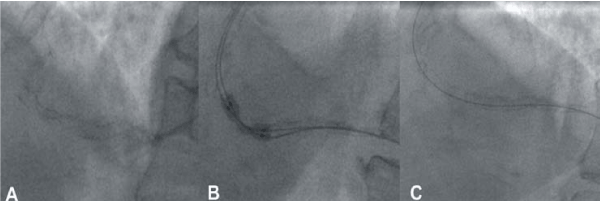

| Figure 2: A - Appearances of the artery following intial stent deployment. The under-deployed stent is clearly visible. B - The double balloon technique for post-dilatation of the under-deployed stent. C - Appearance of the stent following stentablation, with the interrupted stent struts visible. |